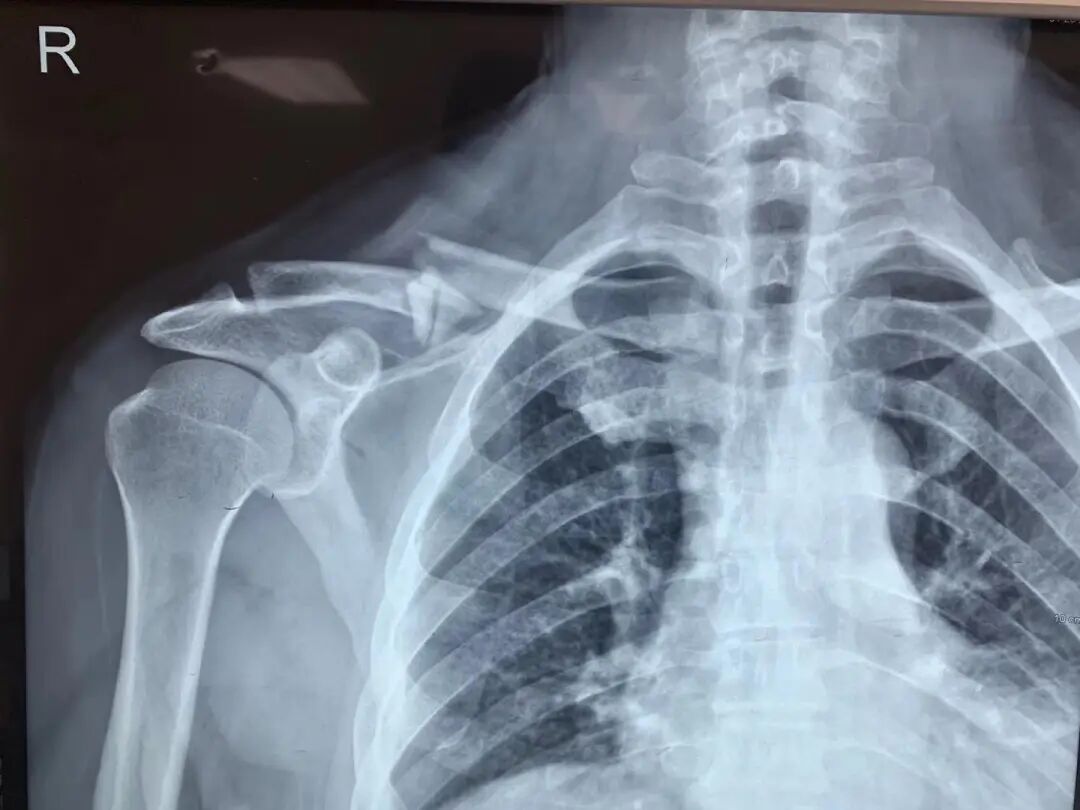

当锁骨骨折发生时,一侧的四肢看起来会有些异常,本应该对称的锁骨会发生一些弯曲。

如果是严重外伤导致的锁骨骨折,也可能伴有周围其它部位的骨折。

例如肩胛骨和肋骨的骨折,此时需要对周围的骨头进行检查,并消除危险因素。